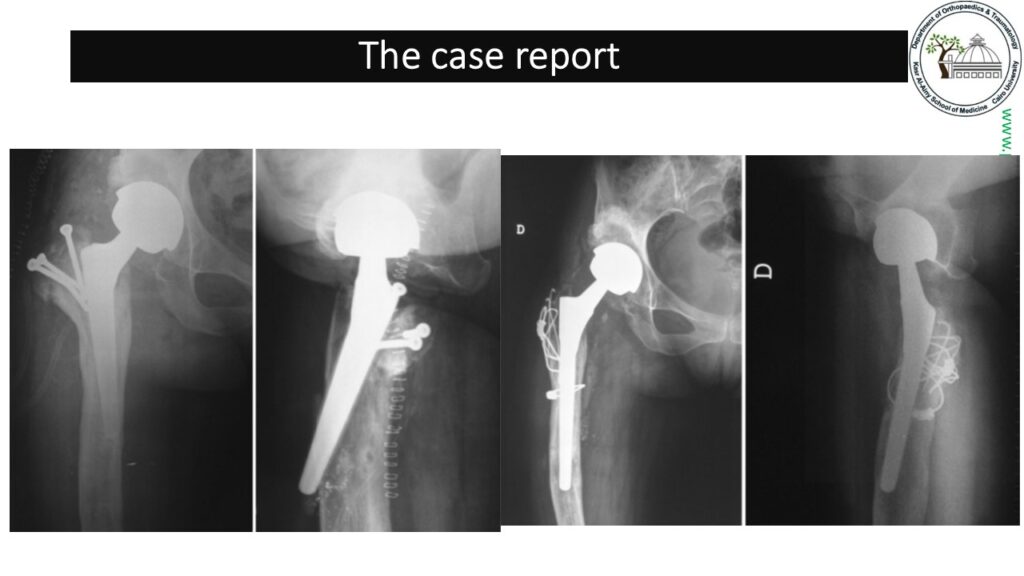

The presented case was operated upon in our pelvic and arthroplasty unit in Cairo University Hospitals. Through a standard posterior approach the cementless acetabular component was safely and well applied. On the femoral side risk of perforation was very high.The choice at hand was between carrying some form of extended trochanteric osteotomy that would preclude the use of a long bypassing stem, which was not ideal for our patient age and level of activity.

The second was to perform a transverse femoral osteotomy before preparing the medullary canal which increases the surgical difficulty. We opted for another solution. The projection of the endofemoral rasping was identified by drilling along that rasping path with a guide pin followed by drilling with 7mm DHS inner drill of the standard triple reader. That opened a strategically placed cortical window for the distal tip of the femoral rasp. Further gradual rasping could be then carried out with no risk of femoral fracture.

With the final rasp in situ, the transverse complete osteotomy was done at the level of the exit of the rasp top. The femur was aligned and after trial reduction an over riding segment from the distal femur was resected. Reduction and plate fixation was carried out with screws inserted avoiding the space for insertion of the definitive stem. Choice of either a cemented or a cementless stem fixation as at the surgeon’s discretion. In our case we opted for a cemented stem for soft bone condition.